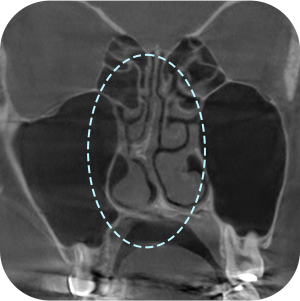

The implant information from the previous surgery is checked

Functional problems such as a deviated septum are checked for

The current implant location is checked

Nasal CT scan, is it necessary?

ASince this is a revision surgery,

a more precise diagnosis is a must!

external appearance and internal functional

problems of the nose are accurately

diagnosed through 3D-CT.